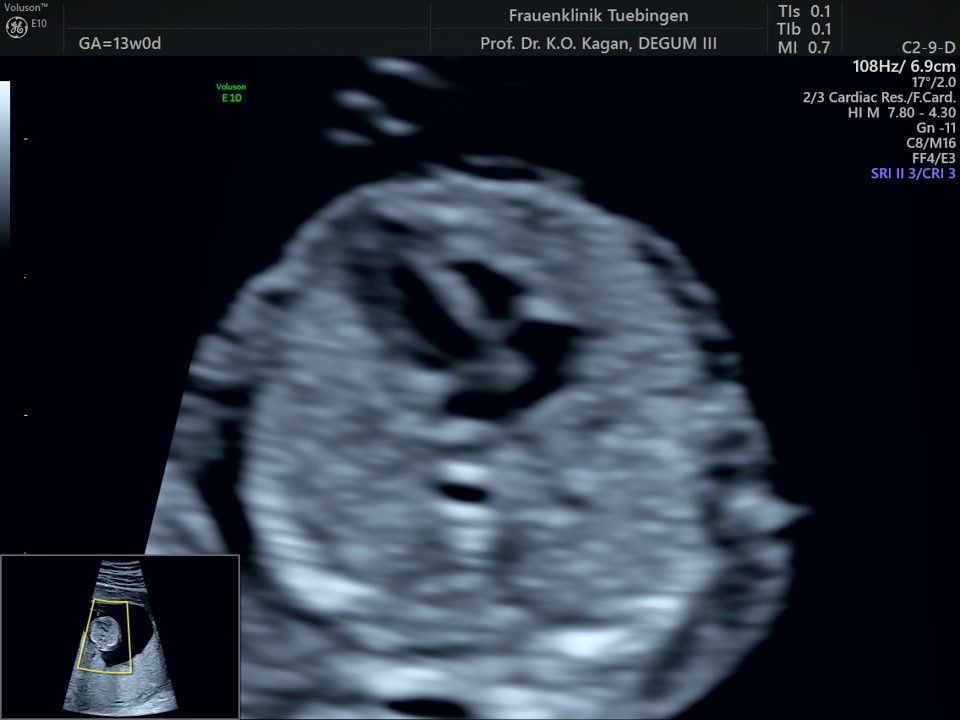

Im Rahmen des Ersttrimester-Screenings untersuchen wir die Organe des Feten mittels Ultraschall. Dabei machen wir auch gerne ein Bild für Sie.

Obwohl der Fet zu diesem Zeitpunkt erst zwischen 5 und 8cm groß ist, lassen sich bereits etwa die Hälfte aller schwerwiegenden Fehlbildungen erkennen bzw. ausschließen. Sollten wir eine Auffälligkeit sehen, werden wir mit Ihnen den Befund und das weitere Vorgehen ausführlich besprechen.

Fetale Anatomie

Herz